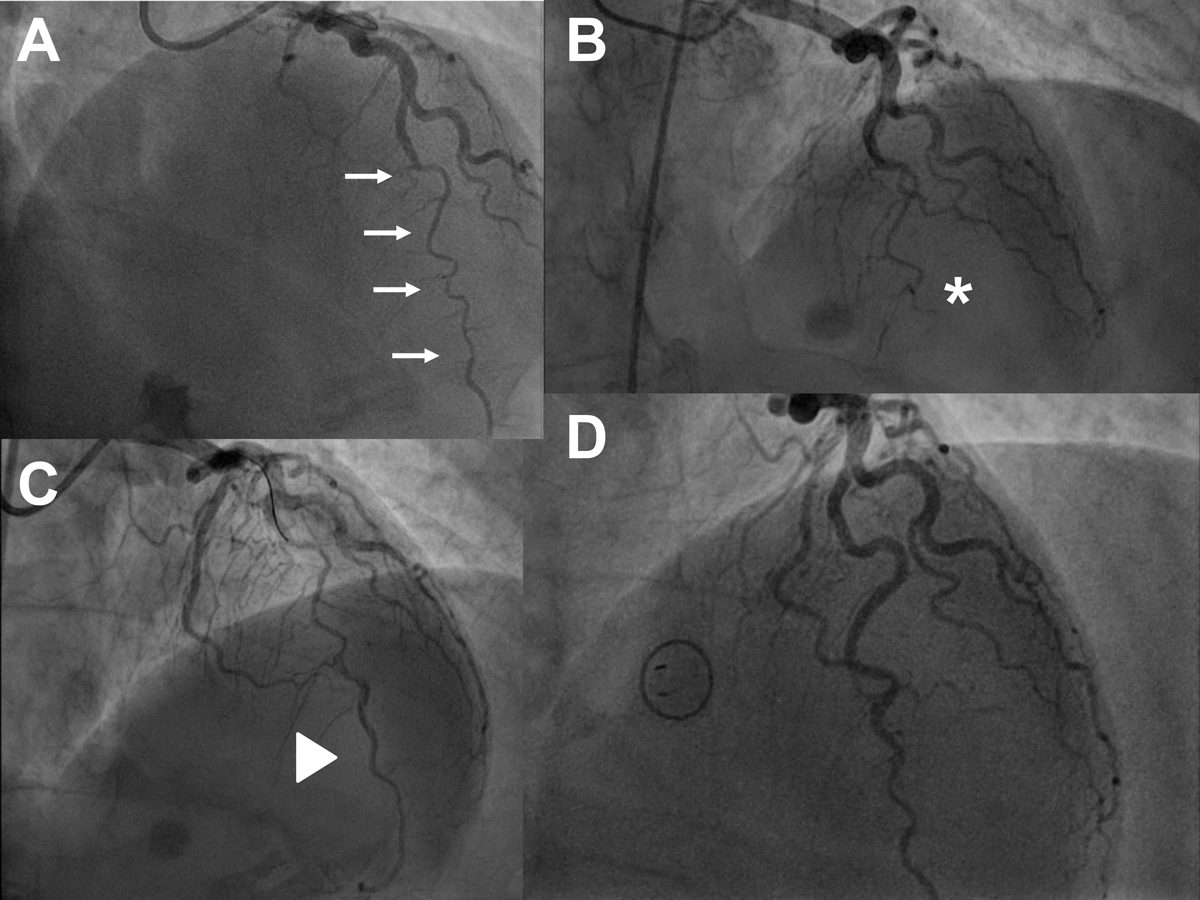

Figure 4 Serial angiograms of a 56-year-old woman with extensive spontaneous coronary artery dissection (SCAD) of the mid to distal left anterior descending artery (LAD; panel A, cranial view, as also in B-D, arrows highlighting the extent of the dissection). A decision for conservative management was made at that time. The guiding catheter and the guidewire were used to optimise angiography but no percutaneous coronary intervention (PCI) was attempted. Panel B: emergency repeat angiogram 10 hours later because of ST-segment elevation myocardial infarction showing complete occlusion of the distal LAD (asterisk). The LAD was treated by PCI using balloon dilation and application of a drug-coated balloon with the aim of preventing secondary re-stenosis after injury to the vessel wall caused by balloon inflation. Panel C: result after PCI, triangle highlighting the re-opened LAD. Panel D: repeat angiography after 6 months showing an open LAD with minimal irregularities of the vessel wall (see also table 4).